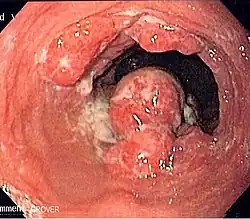

Although an occlusive tumor may be suspected on a barium swallow or barium meal, the diagnosis is best made with an examination using an endoscope. This involves the passing of a flexible tube with a light and camera down the esophagus and examining the wall, and is called an esophagogastroduodenoscopy. Biopsies taken of suspicious lesions are then examined histologically for signs of malignancy.

-

Endoscopic image of Barrett esophagus – a frequent precursor of esophageal adenocarcinoma -

Types

Esophageal cancers are typically carcinomas that arise from the epithelium, or surface lining, of the esophagus. Most esophageal cancers fall into one of two classes: esophageal squamous-cell carcinomas (ESCC), which are similar to head and neck cancer in their appearance and association with tobacco and alcohol consumption—and esophageal adenocarcinomas (EAC), which are often associated with a history of GERD and Barrett's esophagus. A rule of thumb is that a cancer in the upper two-thirds is likely to be ESCC and one in the lower one-third EAC.